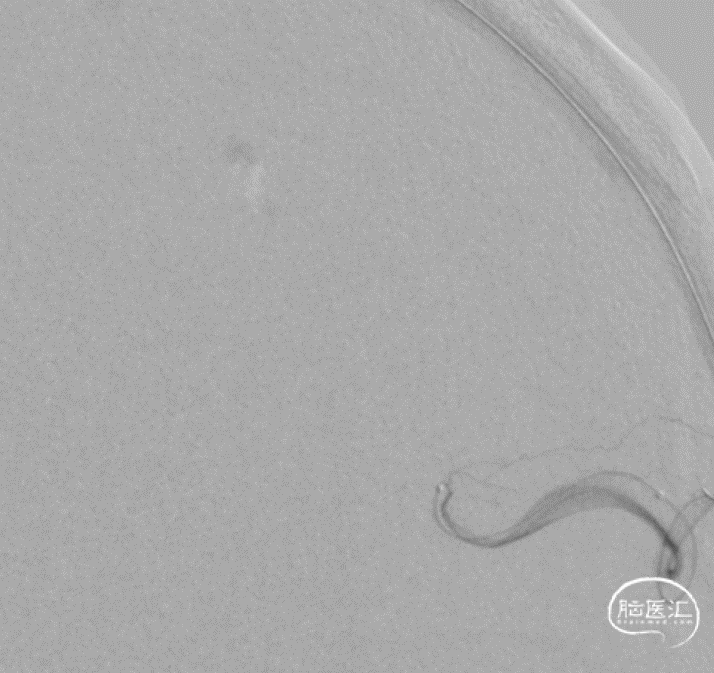

治疗方案:全麻下,静脉入路脑动静脉畸形栓塞术(球囊保护)

术中动脉造影

动静脉联合3d显示引流静脉与矢状窦关系;中天21微导管塑形(半圆)支撑下FATHOM-14导丝超选成功,考虑enchlon10长度不够,截断中管;FATHOM-14 3m交换enchelon10,但阻力大未能到位,中间管也未能到引流静脉入口;头羊作用下apollo3cm超选到位。